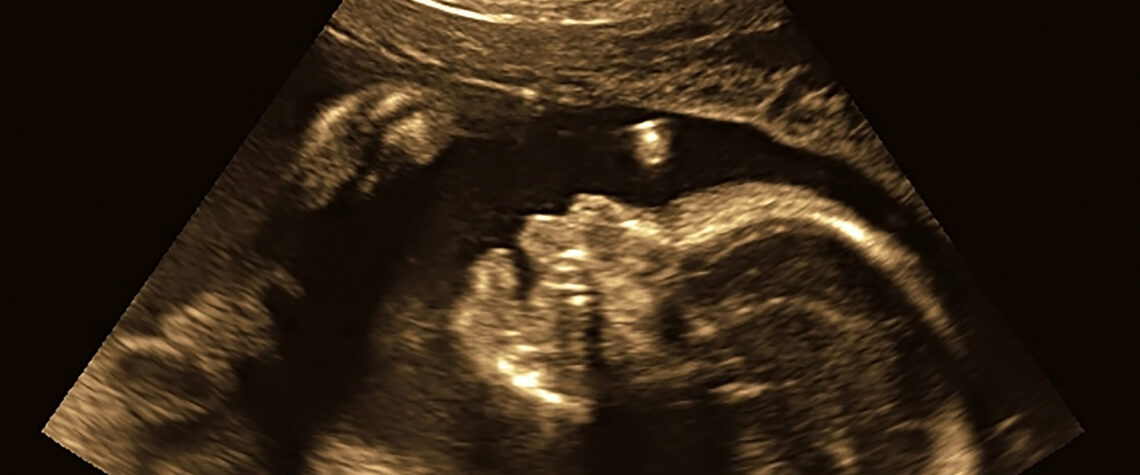

Ultrasounds: Under 500 (2023) ; Over 630 (2024)

Introduction of early prenatal care:

Offers medical attention and emotional support to uninsured pregnant mothers during the first 12 weeks of pregnancy. Healthier pregnancies lead to better outcomes for both children and families!